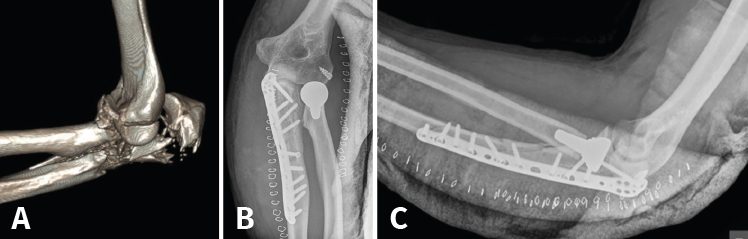

Son lesiones poco frecuentes pero complejas. Es esencial una reconstrucción anatómica precisa del cúbito proximal para recuperar la funcionalidad del codo. La restauración anatómica de la longitud y las dimensiones del cúbito será crucial para la congruencia de la articulación radiocapitelar. Una reconstrucción fallida o inadecuada acabará con dolor persistente y una progresiva degeneración de la articulación. Hay que poner especial atención en 2 fragmentos: la faceta anteromedial de la coronoides y la faceta anterolateral del cúbito, junto a la cresta del supinador. La planificación preoperatoria es vital, por lo que recomendamos la TAC con reconstrucción 3D (Figura 9).

Figura 9. A: imagen en 3D de una fractura proximal compleja de cúbito y radio; B y C: radiografías de control tras la cirugía en otro caso de lesión Monteggia-like.